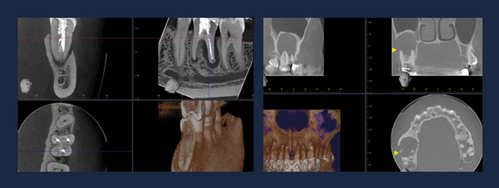

13.30-14.15 CBCT og endodonti/smertetilstander/sinusproblematikk

14.30-15.15 CBCT og implantologi

15.15-16.30 CBCT og periodonti/kjeveortopedi/pedodonti/protetikk